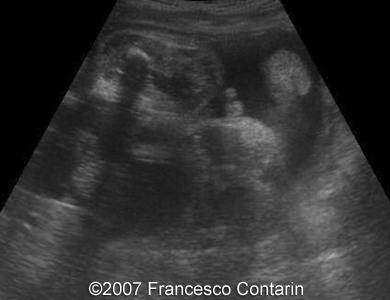

Images 11, 12. 29th week of pregnancy -  coronal plane through normal fetal lips and nose (left); and coronal plane through the fetal skull - normal (right).

11

12